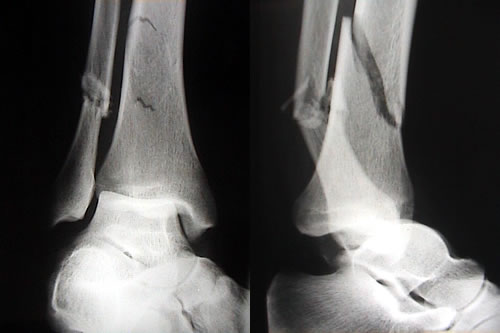

Algunos estudios científicos sugieren que si la enfermedad celíaca no está diagnosticada y tratada quienes la padecen tienen mayores riesgos de sufrir fracturas. Una nueva investigación –publicada en la revista científica World Journal of Gastroenterology– refuerza la relación entre riesgos de fractura y celiaquía, enfermedad que se caracteriza por entorpecer la absorción de los alimentos.

En las pasadas dos décadas diversos estudios científicos abordaron el posible efecto de la enfermedad celíaca sobre la densidad ósea. La osteopenia –disminución en la densidad mineral ósea que puede ser una condición precursora de osteoporosis– y la osteoporosis detectadas a partir de mediciones de densidad ósea –realizadas en esas investigaciones– se han registrado en más del 50 por ciento de los pacientes que tiene enfermedad celíaca. Un meta-análisis de ocho estudios diferentes publicados entre el año 2000 y 2007, en el que participaron 20.995 pacientes y 97.777 personas sin la enfermedad– concluyó que los pacientes con la enfermedad celíaca tienen un 43 por ciento más riesgos de sufrir fracturas.